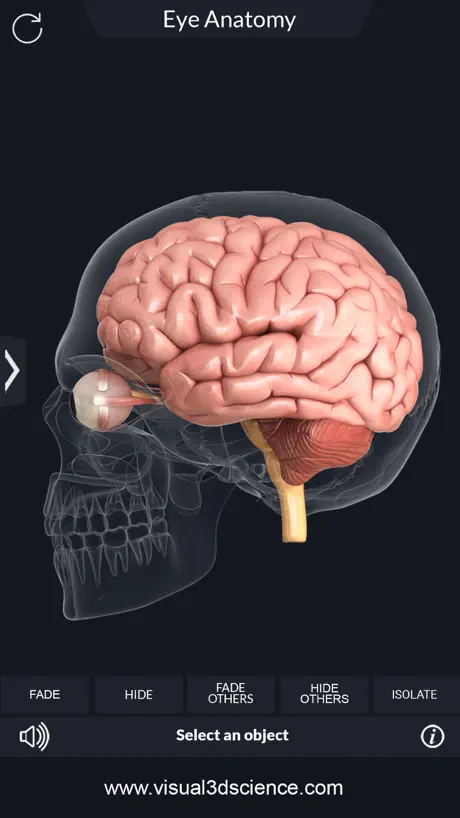

Screenshots